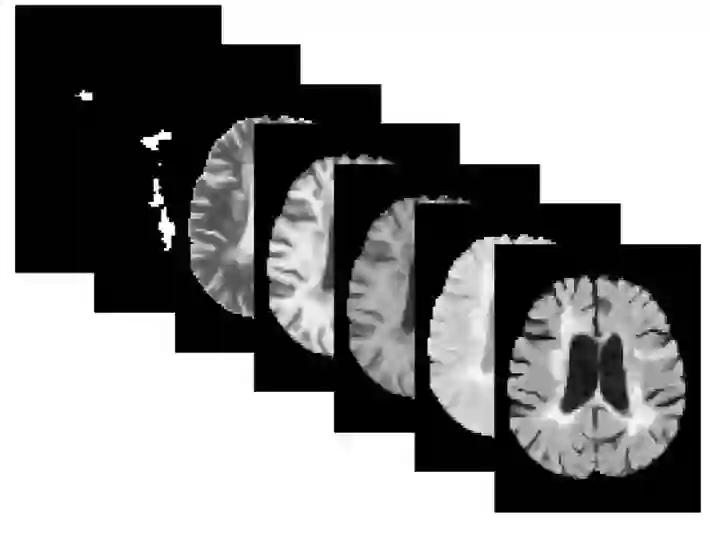

Precision medicine for chronic diseases such as multiple sclerosis (MS) involves choosing a treatment which best balances efficacy and side effects/preferences for individual patients. Making this choice as early as possible is important, as delays in finding an effective therapy can lead to irreversible disability accrual. To this end, we present the first deep neural network model for individualized treatment decisions from baseline magnetic resonance imaging (MRI) (with clinical information if available) for MS patients. Our model (a) predicts future new and enlarging T2 weighted (NE-T2) lesion counts on follow-up MRI on multiple treatments and (b) estimates the conditional average treatment effect (CATE), as defined by the predicted future suppression of NE-T2 lesions, between different treatment options relative to placebo. Our model is validated on a proprietary federated dataset of 1817 multi-sequence MRIs acquired from MS patients during four multi-centre randomized clinical trials. Our framework achieves high average precision in the binarized regression of future NE-T2 lesions on five different treatments, identifies heterogeneous treatment effects, and provides a personalized treatment recommendation that accounts for treatment-associated risk (e.g. side effects, patient preference, administration difficulties).

翻译:为治疗慢性病,如多发性硬化综合症(MS)的精密医学涉及选择一种最能平衡对个别病人的功效和副作用/偏重的治疗方法。尽早作出这一选择很重要,因为寻找有效疗法方面的拖延可能导致不可逆转的残疾累积。为此,我们为慢性病病人提供了第一个通过基线磁共振成像(如果有临床信息,则提供临床信息)进行个性化治疗决策的深神经网络模型。我们的模型(a)预测未来新的和扩展的T2加权(NE-T2)的偏差计数是后续的多重治疗MRI,(b)估计根据预测未来抑制NE-T2损伤对安慰物的不同治疗方案所定义的有条件平均治疗效果(CATE ) 。我们的模型在四个多中心随机临床试验期间从MS病人那里获得的1817年多序列MMSIs专有制数据集(如果有临床信息的话)。我们的模型在五个不同治疗方法的未来NE-T2损伤的双向回归中达到了很高的平均精确度精确度,确定了混合治疗效果,并提供了个人风险处理困难。